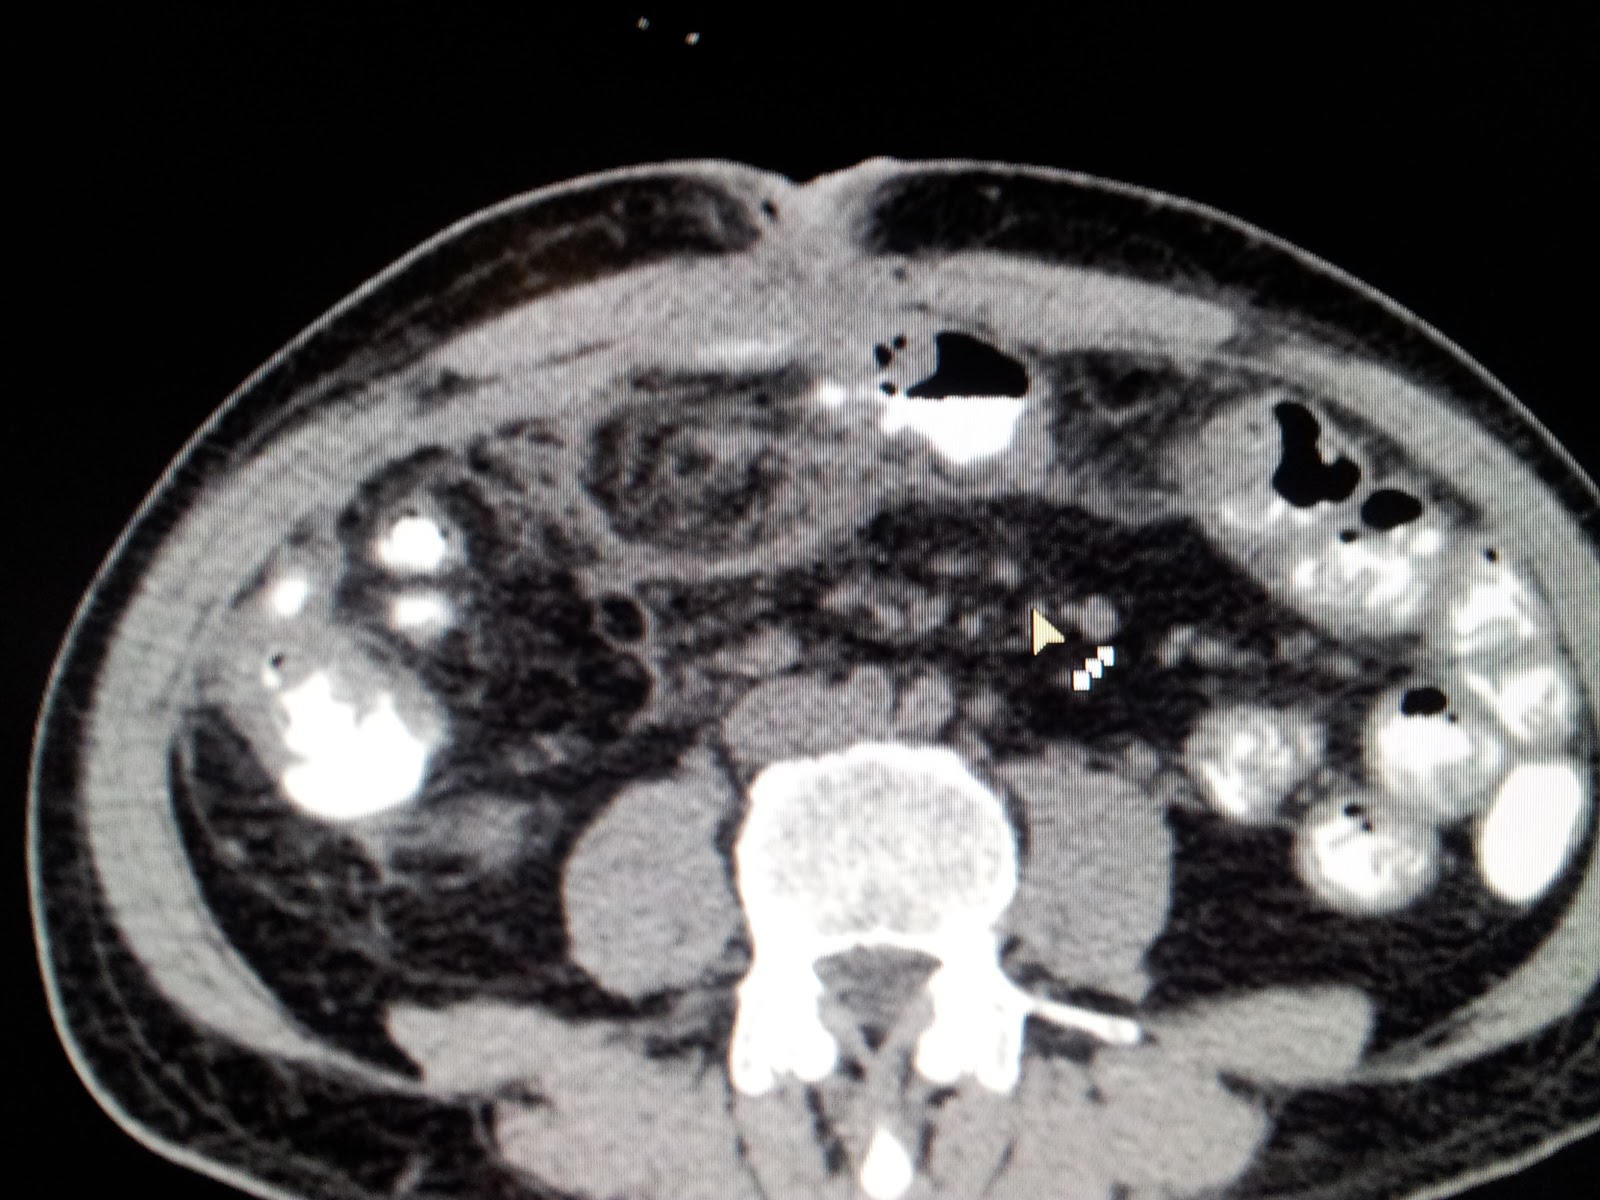

CASE: Chronic alcoholic pancreatitis with pseudocyst in head^-www.drkeyurbhatt.in*

Middle aged male with severe pain in central abdominal pain severe in intensity ,  for 6 months and 25 kg wt loss. DM II For last 6 months..

evaluated and diagnosed as Chronic alcoholic calcific pancreatitis with pseudo cyst in uncinate process of pancreas..

CECT:

SURGERY: LPJ With head coring...

Patient discharged on POD 6. without pain.